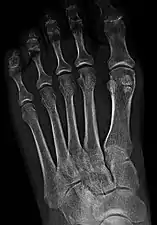

Sesamoid bones at the distal end of the first metatarsal bone of the foot.